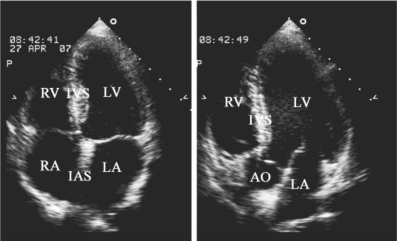

-